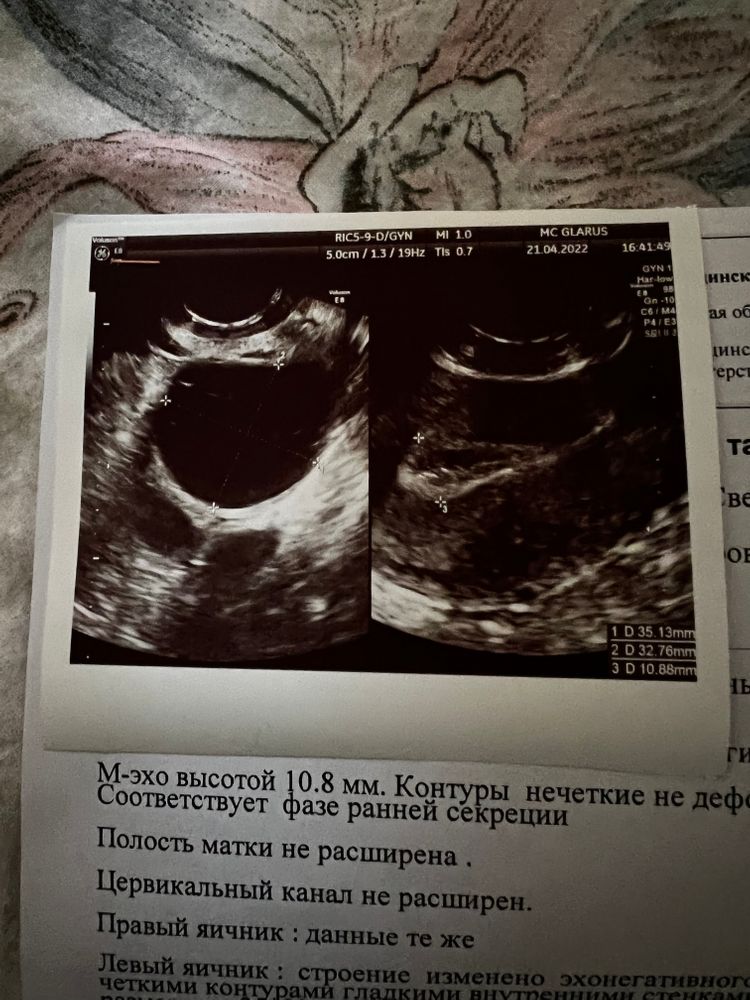

Узи 21 ДЦ

Была стимуляция, на узи 21 ДЦ у меня киста желтого тела.

И вот узи пишет эндометрий соответствует ранней фазе секреции, посмотрела - это 15-18 день. У меня был укол хгч 15.04 и овуляция или 15.04 или 16.04. Уже вроде не ранняя фаза… или я загоняюсь?